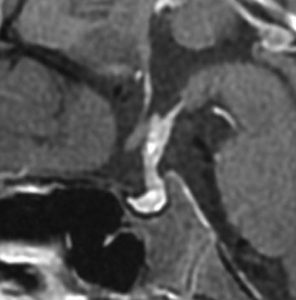

ICE化学療法投与開始から数日で小さくなります

この例は古いので第3脳室開窓術 ETV をしていません。左はICE化学療法前。中央は9日後。右は25日後です。閉塞性水頭症があっても1週間くらいで中脳水道が通って水頭症は改善します。ジャーミノーマであれば,ICE化学療法1コースでかなり縮小するはずです。このような顕著な効果がない時には,逆にジャーミノーマ以外の胚細胞腫瘍が混在していると考えた方がいいでしょう。多くは奇形腫の混在です。